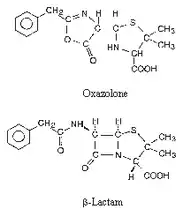

Первый пенициллин (крустозин) был получен в 1942 г. в СССР во Всесоюзном институте экспериментальной медицины, а с апреля 1943 он активно применялся в госпиталях. В сжатые сроки необходимо было установить структуру пенициллина. На тот момент не удалось закристаллизовать собственно пенициллин (предположительно из-за примесей ионов бария), однако после нескольких попыток были выращены кристаллы натриевых, калиевых и рубидиевых солей пенициллина, с которых и были сняты рентгенограммы. Предполагалось несколько структур: содержащая оксазолоновый цикл и содержащая β-лактамный цикл. По результатам расчётов было выяснено, что лактамное кольцо наиболее вероятно в структуре пенициллина. Почти одновременно к таким же выводам пришёл Р. Вудворд по результатам термохимического эксперимента. Как уже было неоднократно отмечено, математическая обработка рентгеновских данных в то время представляла собой весьма нетривиальную задачу. По воспоминаниям Д. Ходжкин, «Структура пенициллина была бы легко определена в начале 1940-х гг., если бы в распоряжении учёных имелись трёхмерные карты патерсоновской функции». Несмотря на все сложности и благодаря большому упорству ей и ее сотрудникам удалось расшифровать структуру пенициллина к 1949 г.